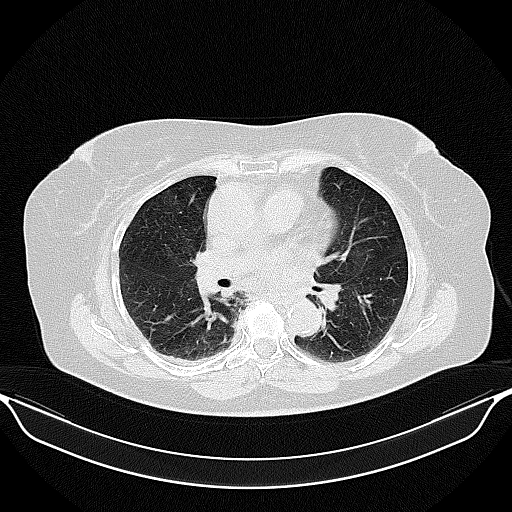

Generated VENOUS CT scan (A→B translation)

Lung window (WL -600, WW 1500 β†’ Low βˆ’1350, High +150)

Actual HU range: [-1259.5, 150.0]